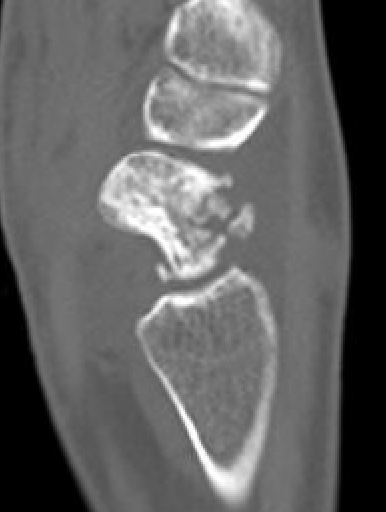

CT

Increased sclerosis of the proximal pole

Fragmentation and collapse of the proximal pole